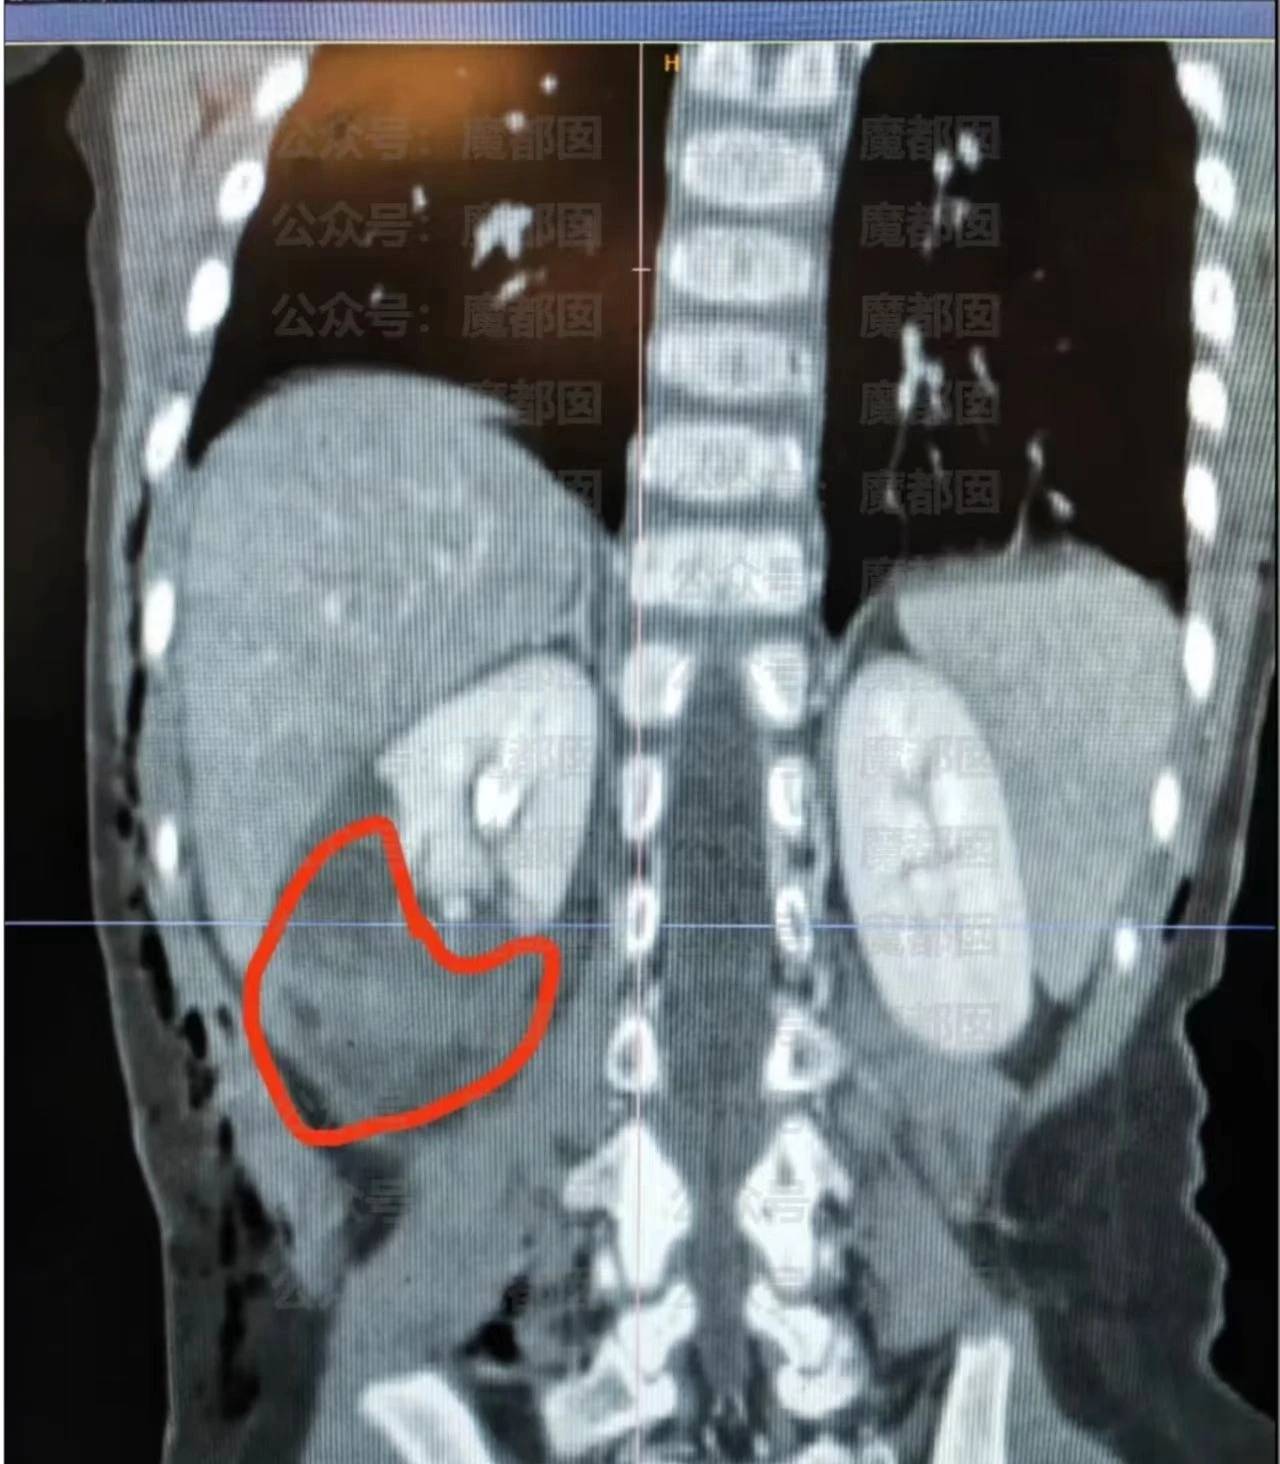

10月16日,四川成都崇州一小区,一只大型黑狗撕咬了一名2岁的小女孩,导致女孩全身多处受伤,其中右肾挫裂伤、右肋骨骨折。